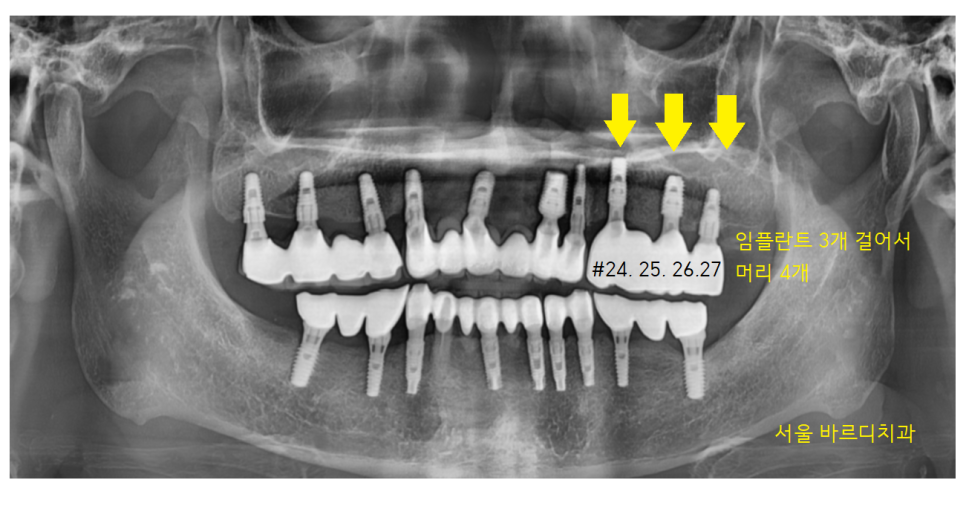

23.08.25

#24,26 임플란트 2개가 들어갔습니다.

예전에는 2개 임플란트에 4개의 어금니를 만들었지만

2개가 4개의 힘을 나눠 했다면

23.11.20

다시 하시는 만큼

3개가 4개의 일을 하도록 하였습니다.

덕풍동 치과에서 튼튼하게 보강하였습니다.

임플란트 치아에 힘을 분배해

부담을 덜어준 것이죠